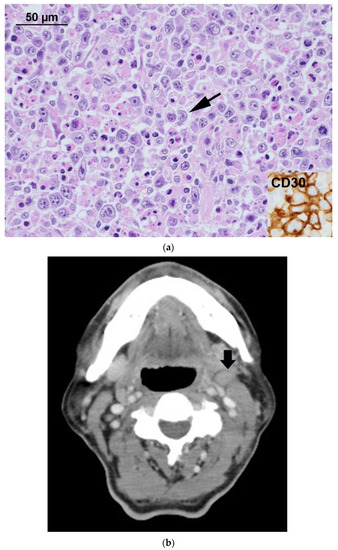

Evolution of 18F-FDG Uptake as a Pitfall of Image Diagnosis for Systemic Anaplastic Large Cell Lymphoma